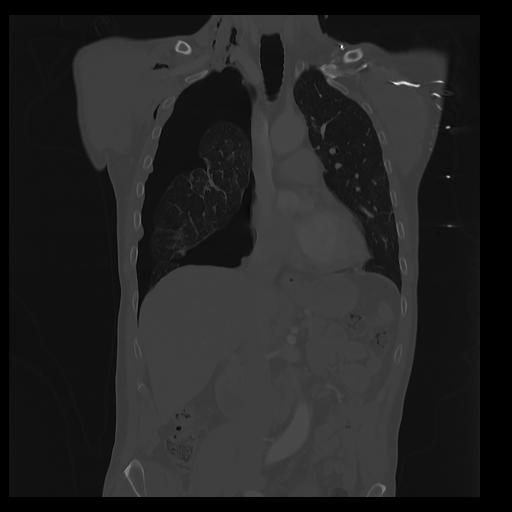

32 PULMON,CE,Coronal,3.000,PULMON,Coronal,